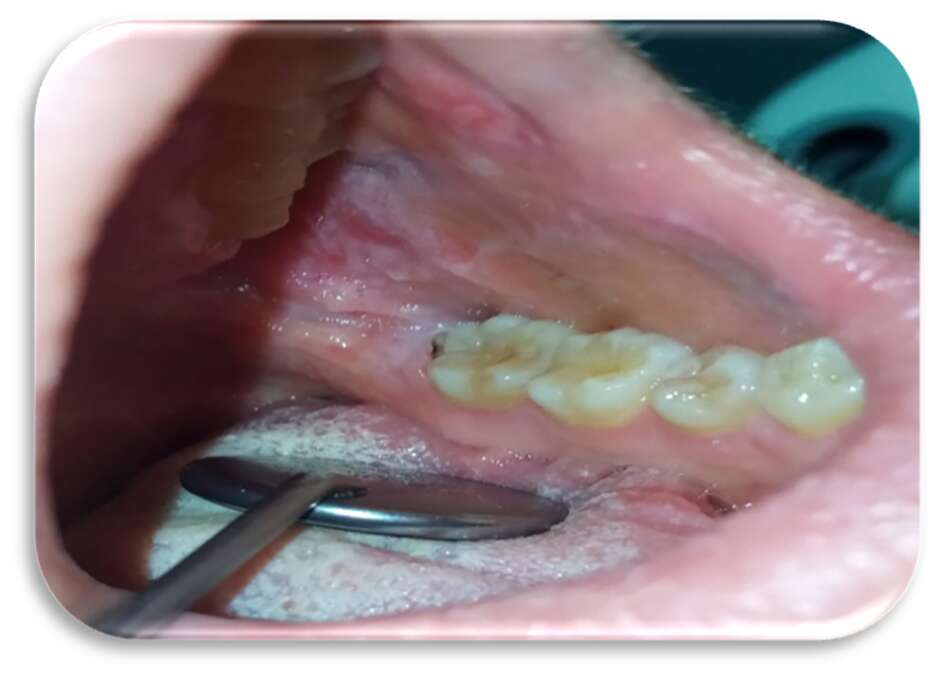

Inizialmente la paziente era stata trattata con collutorio a base di clorexidina 0,2% per circa 12 giorni senza alcun beneficio. Le lesioni si presentavano molto dolenti, erosive ed eritematose bilateralmente e simmetricamente sul ventre linguale (Figure 1 e 2) e sulla mucosa geniena, compatibili con un sospetto quadro clinico di lichen planus orale erosivo.

Sia sui margini linguali che sulle mucose geniene erano presenti, inoltre, segni di morsicatio buccarum e linea alba (Figure 3 e 4).